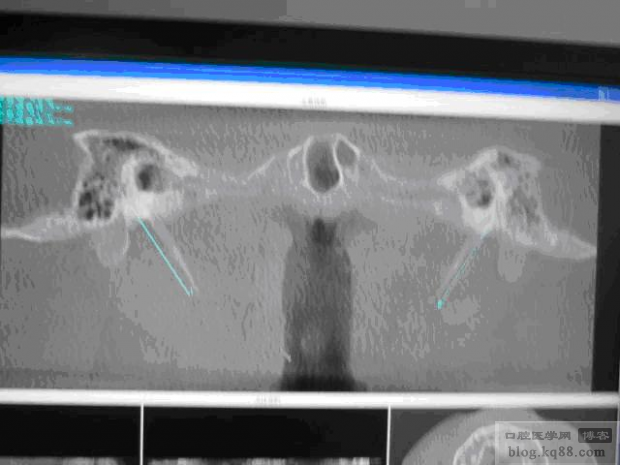

圖4 通過各種調(diào)節(jié) 讓莖突更清晰

圖4